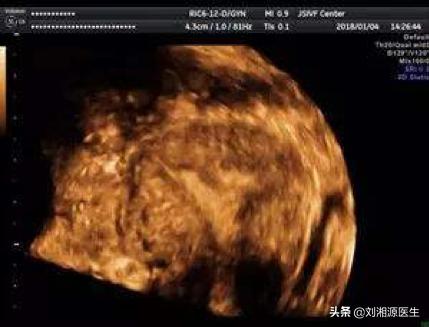

答:(1)目前应用的三维彩超,是诊断宫腔粘连的有效方法之一,因无创、方便、经济,临床广泛应用,能明确粘连部位及程度和宫腔内膜厚度。

(2)部分宫腔粘连时,三维彩超表现为子宫内膜厚薄不均、宫腔粘连处宫腔线消失和内膜薄,而粘连处以外内膜回声正常;

(3)宫腔广泛粘连时,三维彩超显示为宫腔内膜薄,呈细线状,内膜线中断,无周期性改变,或为不规则强回声。

(4)三维彩超不一定均能发现所有病变,敏感性52%,特异性仅11%。